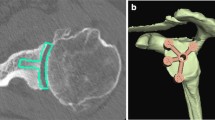

With the advent of the reverse total shoulder replacement that uses a glenoid implant fixed to the scapula with screws, more research was done to understand the anatomy of the scapula medial to the glenoid surface and the glenoid vault. Codsi et al. used three-dimensional CT scans to determine the best locations to place screws from the glenoid articular surface to the body of the scapula [22]. Twenty-seven scapulae were scanned into a custom software program that allowed the manipulation of the scapula to virtually implant screws of different lengths into the bone. Three locations in the scapula body were found that could accommodate long screws. The first was the superior screw, which started in the superior portion of the glenoid and was directed toward the base of the coracoid. The second screw started in the middle of the glenoid and went through the middle of the scapula (Fig. 6.8a–c). The third screw location started on the inferior glenoid surface and was directed along the lateral cortical border of the scapula. The length of the screws could be as long as 75 mm if placed perfectly, but any deviation in the angle of the insertion by 15° would alter the length of the screws between 17 and 30 mm. When the constraint of an implant was introduced, the lengths of the screws were much shorter as well. Using the current implant designs that feature a central screw or fixation, this screw can be placed in the location described as the central screw in this study. The other superior and inferior screw locations are not typically useful with the current implants available because they do not allow for the high angle of insertion needed to place the screw in those positions of the scapula.

Cross-sectional CT scan images of a scapula with a central screw hole starting at the center of the glenoid articular surface and exiting at the junction of the scapula spine and medial border of the scapula (Reprinted from Codsi et al. [22] with permission from Elsevier). (a) Cross section of the scapula 2 cm medial to the glenoid surface, (b) Cross section in the middle of the scapula, (c) Cross section 2 cm from the medial border of the scapula